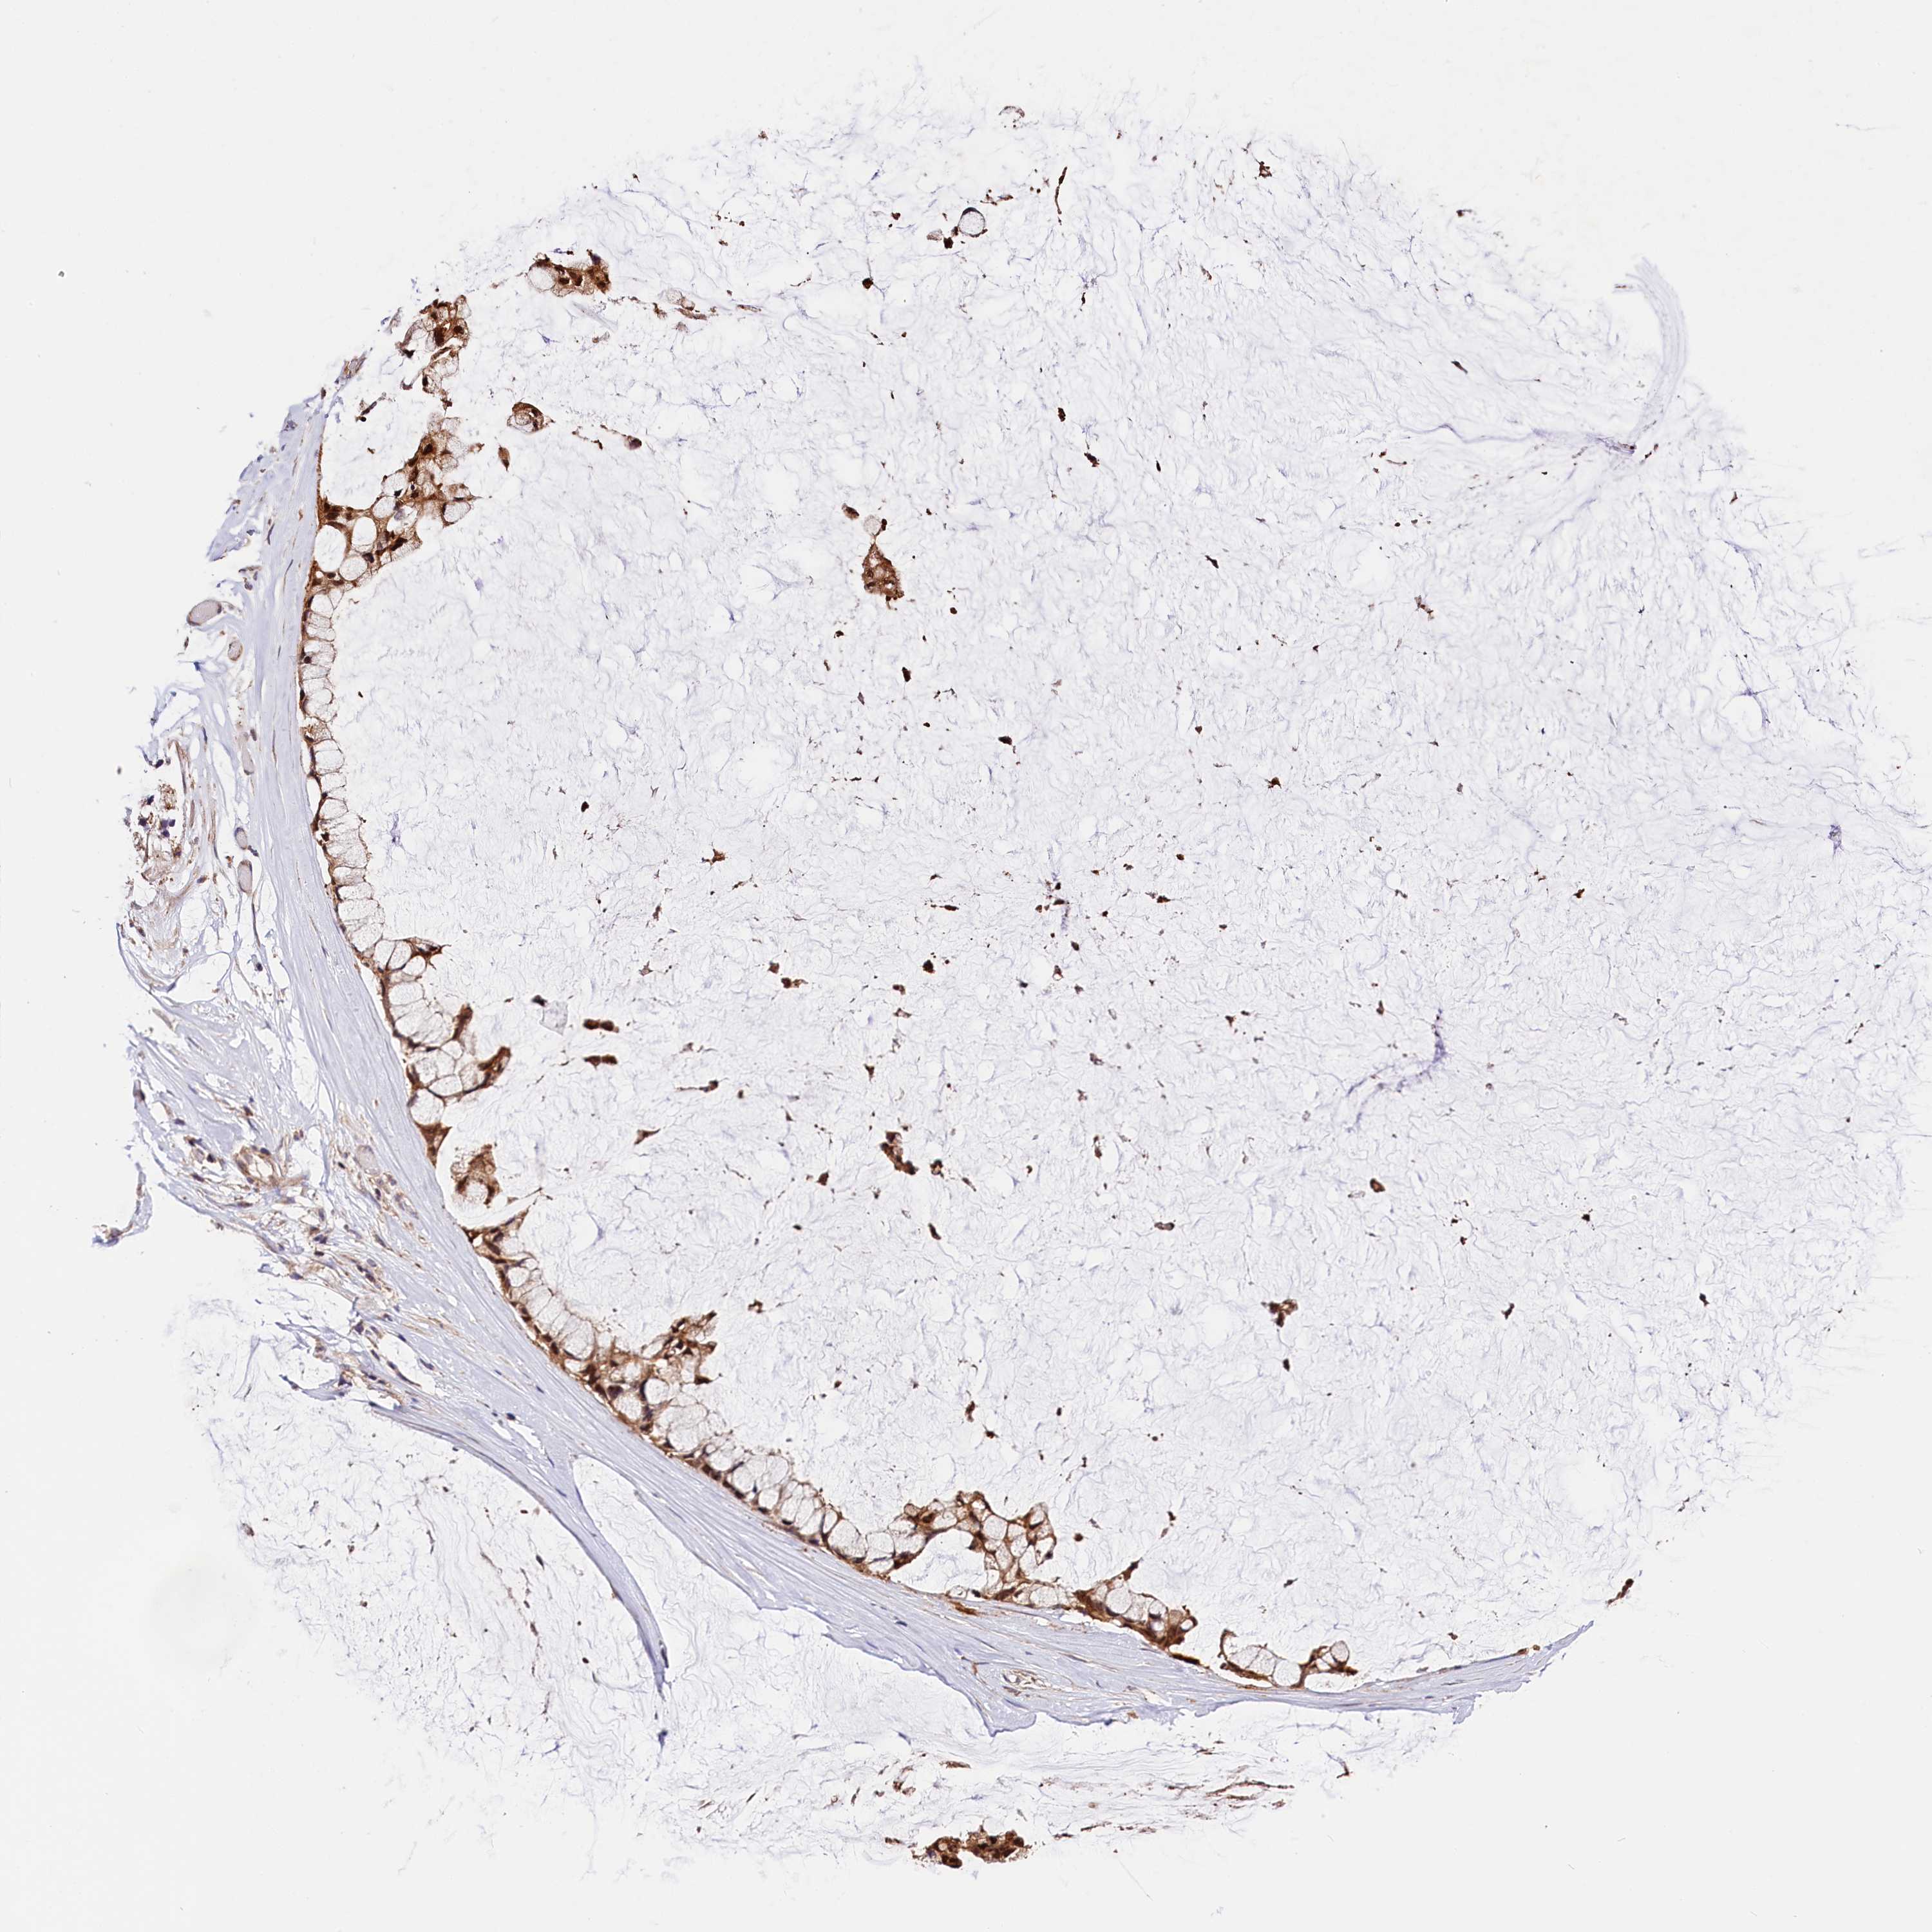

OVARIAN CANCER - Protein expressioni

A mouse-over function shows sample information and annotation data. Click on an image to view it in a full screen mode. Samples can be filtered based on level of antibody staining by selecting one or several of the following categories: high, medium, low and not detected. The assay and annotation is described here.

Note that samples used for immunohistochemistry by the Human Protein Atlas do not correspond to samples in the TCGA dataset.

Antibody stainingi

Antibody staining in the annotated cell types in the current human tissue is reported as not detected, low, medium, or high, based on conventional immunohistochemistry profiling in selected tissues. This score is based on the combination of the staining intensity and fraction of stained cells.

Each image is clickable and will lead to virtual microscopy that enables deeper exploration of all samples and also displays staining intensity scores, fraction scores and subcellular localization as well as patient and tissue information for each sample.

Antibody HPA041710

Antibody HPA041796

Staining

High

Medium

Low

Not detected

Intensity

Strong

Moderate

Weak

Negative

Quantity

>75%

75%-25%

<25%

None

Location

Nuclear

Cytoplasmic/membranous

Cytoplasmic/membranous,nuclear

Cystadenocarcinoma, serous, NOS

Carcinoma, endometroid

Cystadenocarcinoma, mucinous, NOS

Carcinoma, NOS